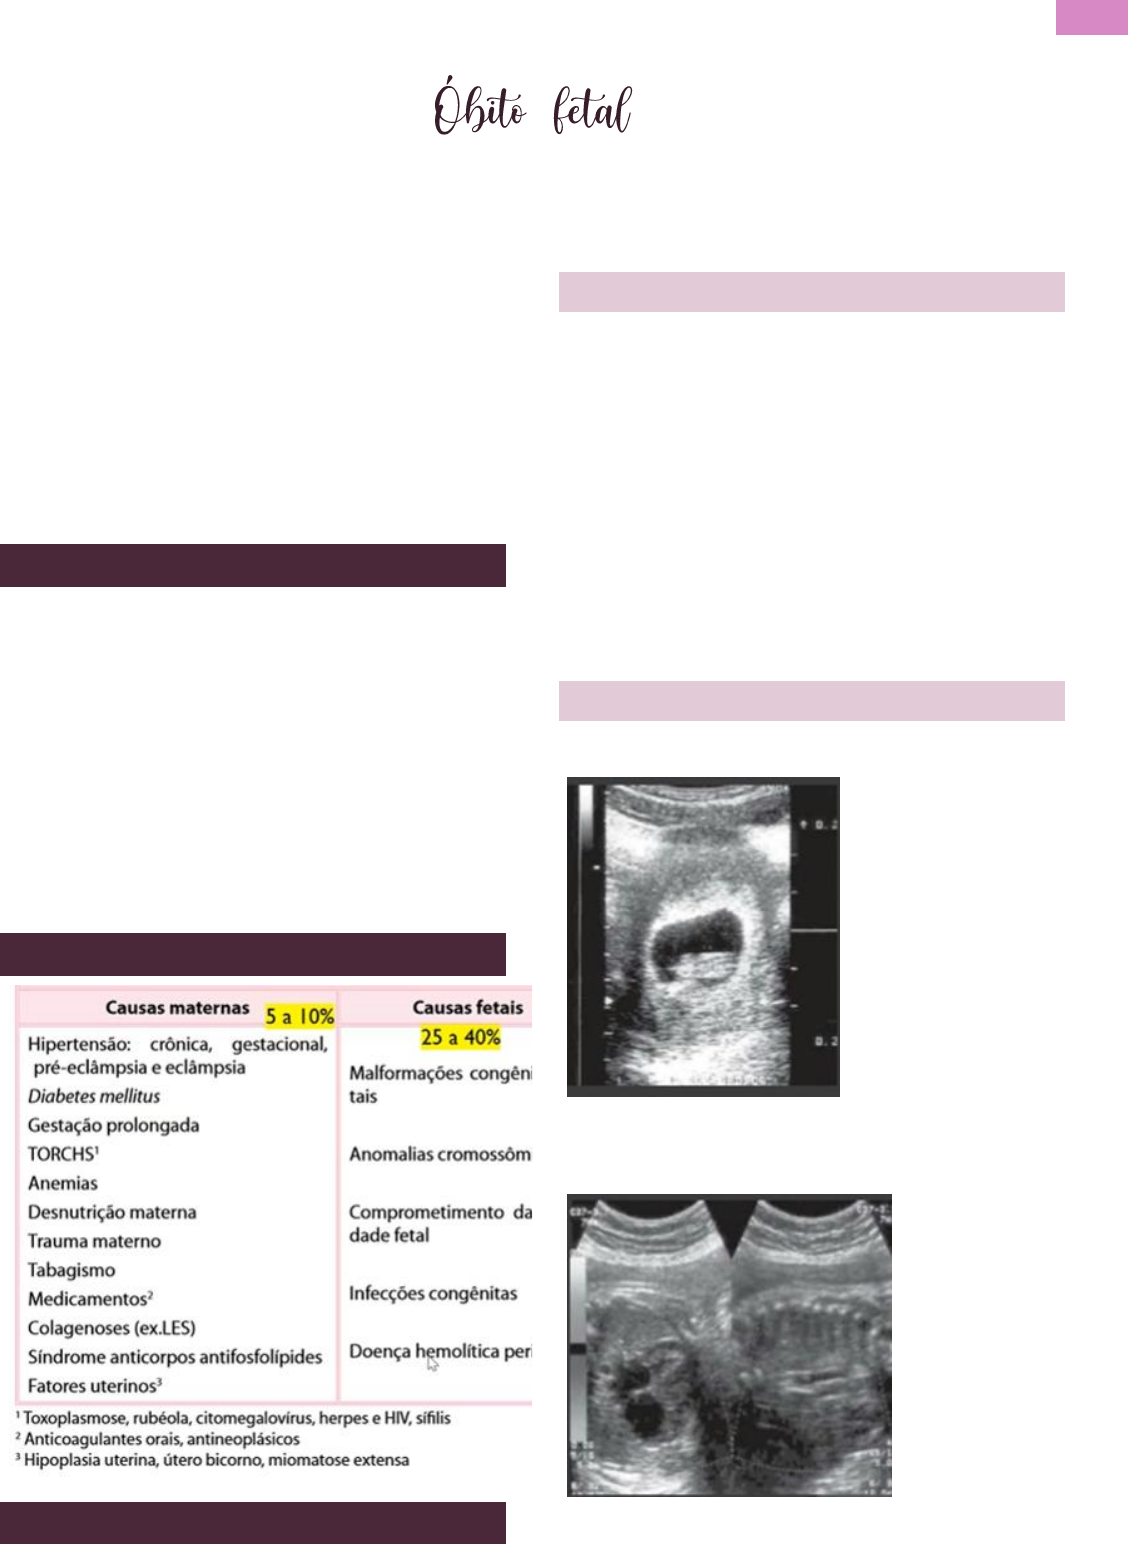

1. Ultrassonografia: padrão ouro para o

diagnóstico de óbito fetal. Ausência de

movimentos fetais e batimentos cardíacos;

Sinais de óbito antigo: superposição de ossos

do crânio (Spalding), hiperflexão da coluna

vertebral (Hartley), sinal do halo craniano

(Devel), Gases na circulação fetal (robert).

ULTRASSONOGRAFIA

- Ausência de atividade cardíaca registo ao doppler

- Ausência de fluxo sanguíneo. Falta de sinal ao

doppler.